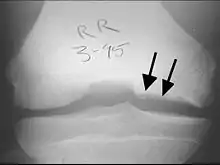

TOC generalmente causa dolor e hinchazón de la articulación afectada y bloqueos de la circulación. El examen físico revela un derrame, sensibilidad y crepitación. El TOC puede ser difícil de diagnosticar porque los síntomas parecen a otras enfermedades. Sin embargo, la enfermedad puede ser confirmado por los rayos X, la tomografía computarizada (CT) o imágenes de resonancia magnética (MRI) explora. OCD está clasificada por estas técnicas de imagen, o por artroscopia de la articulación, y representada en las fases (I, II, III y IV), de la progresión de la enfermedad. Tras el diagnóstico de la enfermedad puede ser tratado, dependiendo de su gravedad, por la reparación del cartílago.[5][6] El tratamiento no quirúrgico rara vez es una opción, ya que el cartílago tiene una limitada capacidad para curar. Como resultado, incluso moderados casos requieren algún tipo de cirugía. Cuando sea posible, no el tipo de gestión como protegidas peso (parcial o no del peso) y la inmovilización se utilizan. El tratamiento quirúrgico varía ampliamente e incluye la perforación de lesiones artroscópicas intactas, la seguridad de las lesiones del cartílago solapa con clavijas o tornillos, la perforación y la sustitución de cartílago enchufes, trasplante de células madre, y reemplazo de articulaciones.

En osteocondritis disecante, fragmentos de cartílago o de hueso se aflojan dentro de una articulación, provocando dolor e inflamación. Estos fragmentos se refieren a veces como los signos comunes.[8] El TOC es un tipo de osteocondrosis en el que una lesión se ha formado en la capa de cartílago en sí, dando lugar a la inflamación secundaria. TOC afecta más comúnmente a la rodilla, aunque puede afectar otras articulaciones como el tobillo o el codo.

Las denuncias individuales por lo general consisten en síntomas mecánicos incluyendo dolor, hinchazón, captura de bloqueo, y dando paso, el síntoma principal puede ser una restricción en el rango de movimiento.[9] Los síntomas se presentan típicamente en las primeras semanas de la etapa I, sin embargo, el inicio de la fase II se produce en cuestión de meses y ofrece poco tiempo para el diagnóstico. La enfermedad progresa rápidamente más allá de la etapa II, como lesiones TOC moverse rápidamente de los quistes estable o fisuras a fragmentos inestables. Los síntomas no específicos, causada por lesiones similares, tales como esguinces y distensiones, puede retrasar el diagnóstico definitivo.[10]

La exploración física suele revelar un derrame, la ternura, y crepitación. El dolor puede extenderse al principio, pero a menudo vuelve a un conjunto bien definido como el punto focal de la lesión progresa. Así como las cuotas de los síntomas del TOC con enfermedades comunes, fractura osteocondral aguda tiene una presentación similar con ternura en la articulación afectada, pero generalmente se asocia con una hemartrosis grasos. Aunque no hay marcha patológica significativa o anomalía alineación característica asociada con este trastorno, el paciente puede caminar con la pierna afectada en rotación externa en un intento de evitar la interacción de la espina tibial en la cara lateral del cóndilo interno del fémur.[11]